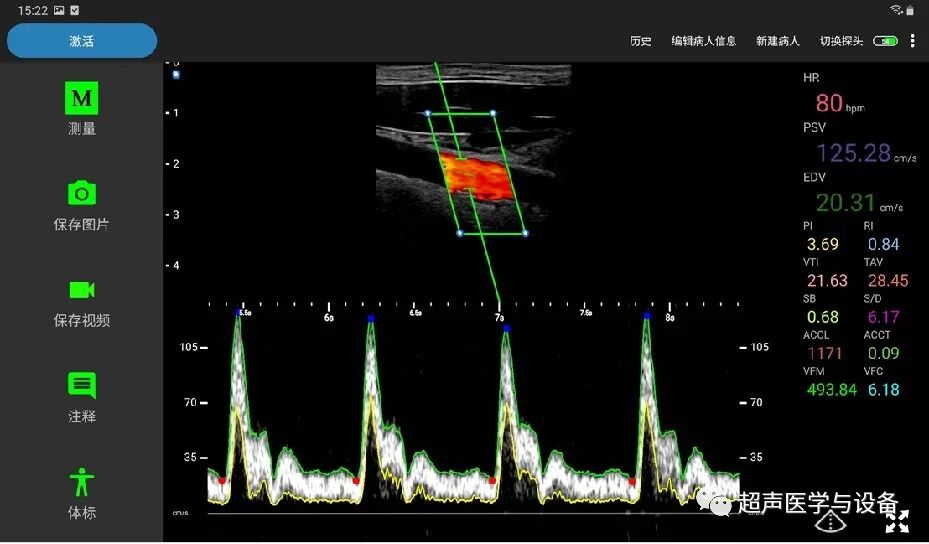

PW自动测量及评估功能

索诺星超声怎么样【一文盘点】市场主流掌上超声_https://www.jmylbn.com_新闻资讯_第21张

索诺星超声怎么样【一文盘点】市场主流掌上超声_https://www.jmylbn.com_新闻资讯_第22张

iM10支持二维码扫描新建病人信息来更高效快捷的输入病人信息帮助医生减少输入时间,并且更加准确与全面。针对不同部位个性化参数预设,专机专用,无需重复调节参数,初学者也轻松上手。同时它内涵丰富,具备PW自动测量与评估功能、IMT自动测量与评估功能、脂肪自动测量与评估功能、穿刺针针尖增强功能等高级功能,堪称“掌超界的杠把子”!